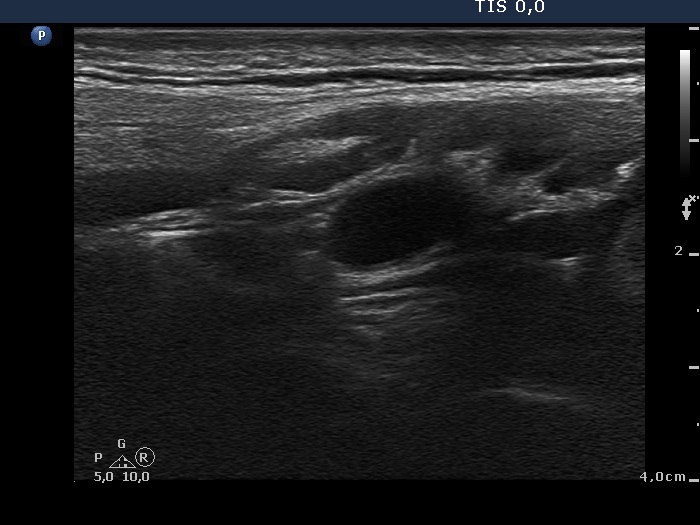

Lymph nodes - case 1096 (ultrasonographic picture 13)

Above the right lobe, longitudinal scan.